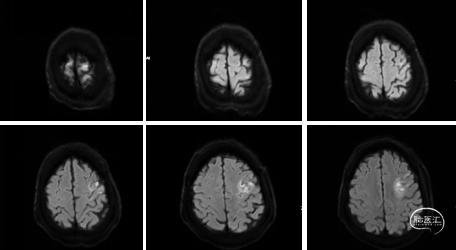

术前影像

术前MRI。

1、左侧颈内动脉(眼动脉发出之前)严重狭窄或闭塞(左侧后交通动脉开放、左侧颈外动脉一左侧颈内动脉侧支循环开放)。

2、右侧颈内动脉(眼动脉发出之后)重度狭窄(右侧后交通动脉开放)。

3、右侧大脑中动脉中-重度狭窄。